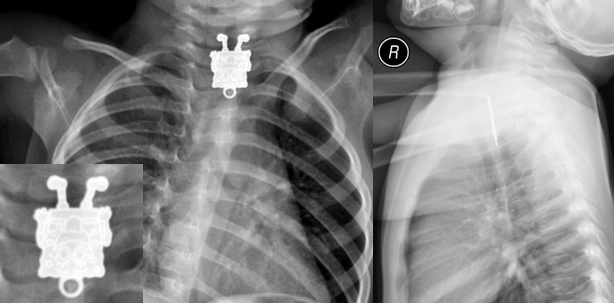

Dr. Ghofran Ageely vom King Abdulaziz University Hospital in Jeddah staunte nicht schlecht, als sie die Röntgenbilder eines Kleinkindes auswertete. In der Seitenansicht sah es aus, als würde eine Nadel oder ein anderer schlanker Gegenstand in der Speiseröhre des Kindes stecken.